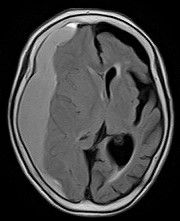

臨床試験において、被験者約1800人の内、17%に脳の出血、12%に脳の腫れがみられたということです。これらのほとんどのケースでは症状が無かったようですが、一部の被験者は副作用を理由に投与を中止する必要があったと報告されています。そのほか、記憶に関係する海馬萎縮は予防しますが原因不明の全脳萎縮をきたします。